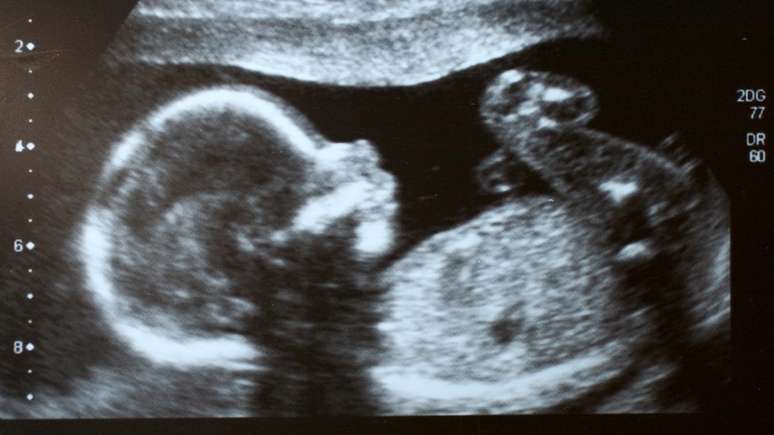

O caso de Itzamara foi descoberto ainda na gestação, por meio de um ultrassom (imagem ilustrativa)

Mónica Vega estava no sétimo mês de gestação quando o médico notou algo muito raro em um exame de ultrassom. As imagens mostravam dois cordões umbilicais, mas Mónica não estava grávida de gêmeos.

Era sua própria bebê, Itzamara, que carregava um feto no abdômen. O feto carregando um feto foi identificado em Barranquilla, na Colômbia.